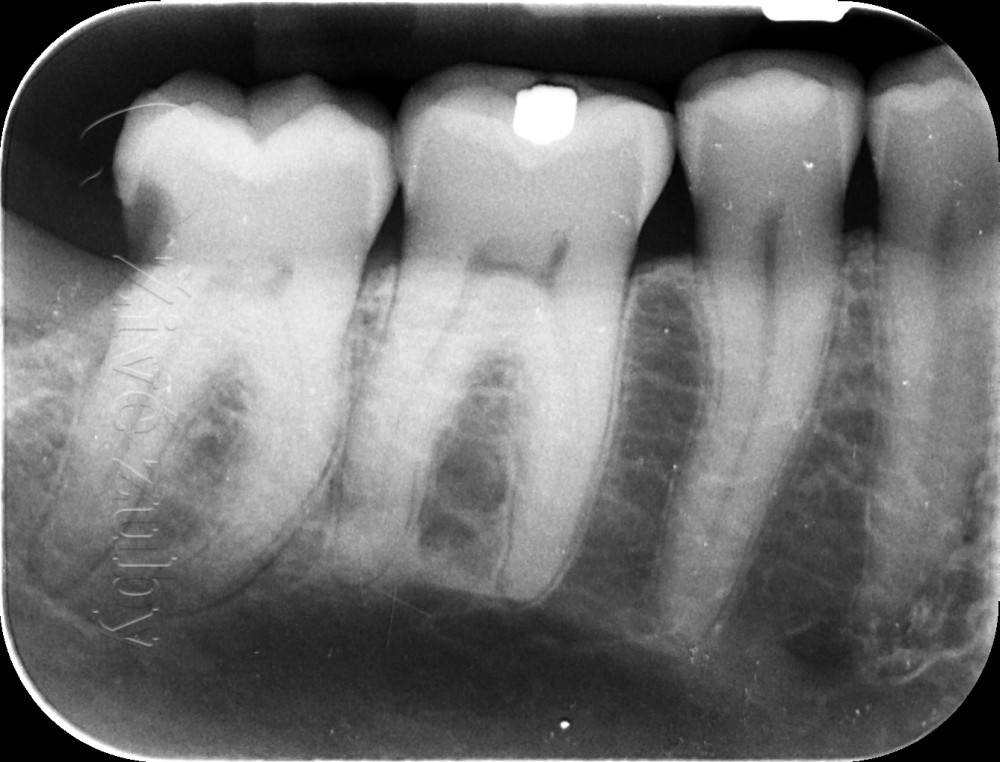

Ošetření hlubokých kazů

Výchozí stav  ——-> Kontrola po 2 letech ——--> Kontrola po 3 letech

Ošetření obtížně dostupných kazů